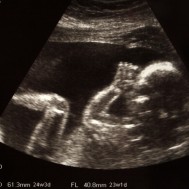

Mam: Pregnant 25 weeks (Baby 23 weeks)

Your uterus is filling in the sides of your abdomen, and moving upward, to make more room for baby!

You should be able to feel lots of movement from this stage on as well as your baby will be moving and kicking in your tummy. [2]